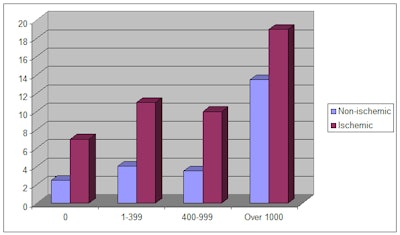

PET scan results [61,80]. Studies

have demonstrated a stepwise increase in cardiac event rates

with increasing CAC score for any level of perfusion abnormality

[61,80,87]. In fact, increasing CAC

score was associated with an increased cardiac event rate even

without the presence of ischemia on PET perfusion imaging (i.e:

a normal perfusion exam) [61]. In patients with normal PET

perfusion exams, the annualized event rate for patients with a

CAC score of zero ranged from 0.7-2.4%, while the rate was 3-11%

for patients with a CAC score above 400 [95,107]. For patients

with ischemia on PET perfusion imaging, the event rate has been

shown to be 8.2% for those without CAC, and over 20% for those

patients with a CAC score over 1000 [87]. The wide range of

event rates was related to evaluation of both symptomatic and

asymptomatic patients [95].

Reproduced from [61]. x-axis indicates CAC score; y-axis indicates annualized event rate (%/yr) |